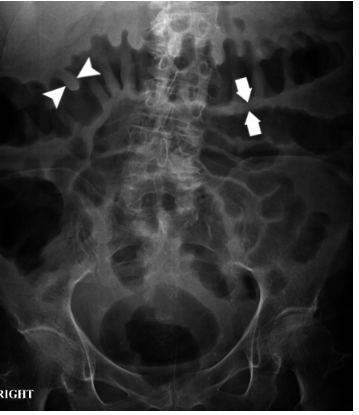

Q

What sign does this AXR show? [1]

What pathology does this indicate? [1]

A

Mucosal thickening - ‘thumbprinting’

This patient presented with an exacerbation of symptoms of ulcerative colitis.